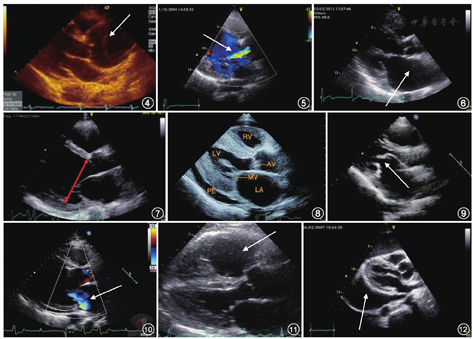

| 升主动脉 | <36 mm | 升主动脉增宽、升主动脉夹层(图4) | 高血压、动脉硬化、结缔组织病、马方(Marfan)综合征 | 测量时间点:舒张末期主动脉瓣关闭 | |

| 主动脉瓣 | 可见右冠瓣和无冠瓣 | 主动脉瓣钙化、狭窄及反流(图5) | 老年退行性瓣膜病常累及主动脉瓣 | 主动脉瓣狭窄时需注意有无瓣上或瓣下异常结构导致的狭窄 | |

| 左心房 | 前后径 | 左心房扩大(图6) | 高血压、房颤 | 收缩末期测量房壁内膜至内膜的最大垂直距离 | |

| 男性<3.9 cm | |||||

| 女性<3.7 cm | |||||

| 左心室 | 舒张末期室壁厚度<1.1 cm | 左心室扩大(图7)、左心室肥厚(图8) | 心肌病、冠心病高血压、心肌病、心肌淀粉 | 舒张末期测量内膜至内膜的垂直距离,取样线置于二尖瓣瓣尖水平并垂直于室壁 | |

| 左心室舒张末径男性<5.5cm女性<5.3cm | 样变等 | 老年人常见室间隔基底段增厚,亦称S形室间隔 | |||

| 二尖瓣 | 可见二尖瓣前后叶 | 二尖瓣钙化、二尖瓣狭窄(图9)、二尖瓣反流(图10) | 二尖瓣狭窄常见于风心病 | 此切面是观察有无二尖瓣脱垂的重要切面 | |

| 右心室 | 前后径<3.0 cm | 右心室扩大(图11) | 先天性心脏病、右心室容量负荷过重(三尖瓣反流)、右心室压力负荷过重(肺动脉高压) | 右心室大小一般为左心室的1/3~1/2,当左、右心室比例接近甚至右心室超过左心室时,提示右心室扩大 | |

| 心包 | 心包积液(图12) | 炎症、甲状腺疾病、肾功能不全、肿瘤等 | 微量生理性心包积液多位于左心室后壁房室沟处,且在舒张期消失 | ||